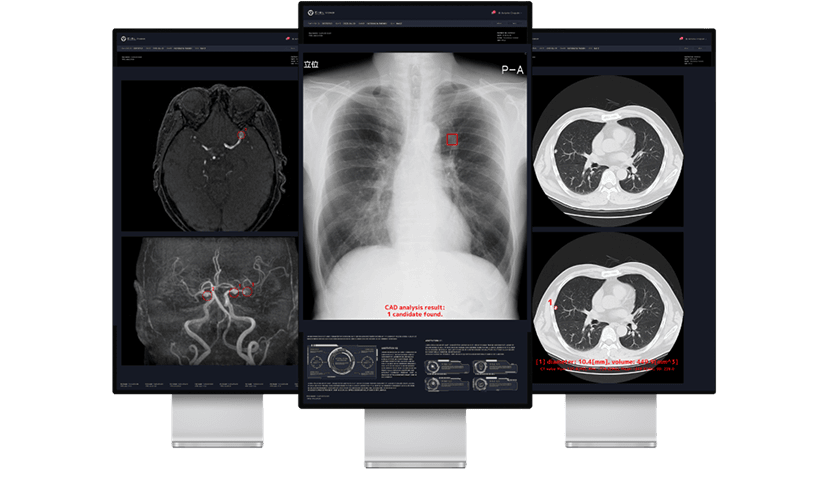

胸部CT画像から肺結節の候補領域を検出

胸部CT画像から肺野領域において、肺結節候補領を自動検出し、その体積と最大径を計測することで、医師の読影診断を支援するソフトウェアです。

胸部X線画像における包括的な

読影支援を提供

胸部X線画像から肺結節・浸潤影・無気肺・間質性陰影候補を検出する機能に加えて、胸腔内の空気含有面積・肋骨横隔膜角・心胸郭比・縦隔幅・大動脈弓径を自動計測する2つのソフトウェアを統合した新たな製品です。

MRA診断を進化させる

脳動脈瘤検出サポートテクノロジー

脳MRA画像から嚢状動脈瘤に類似した領域(2mm以上)を検出することで、医師による読影をサポートします。本ソフトウェアを併用して読影した場合、医師単独での読影感度68.2%は77.2%に大幅に向上しました(放射線科医5年未満:69.6% → 81.2%、放射線科医5年以上:77.2% → 82.0%、脳神経外科医6年未満:53.7% → 62.3%、脳神経外科医6年以上:77.0% → 88.5%)。